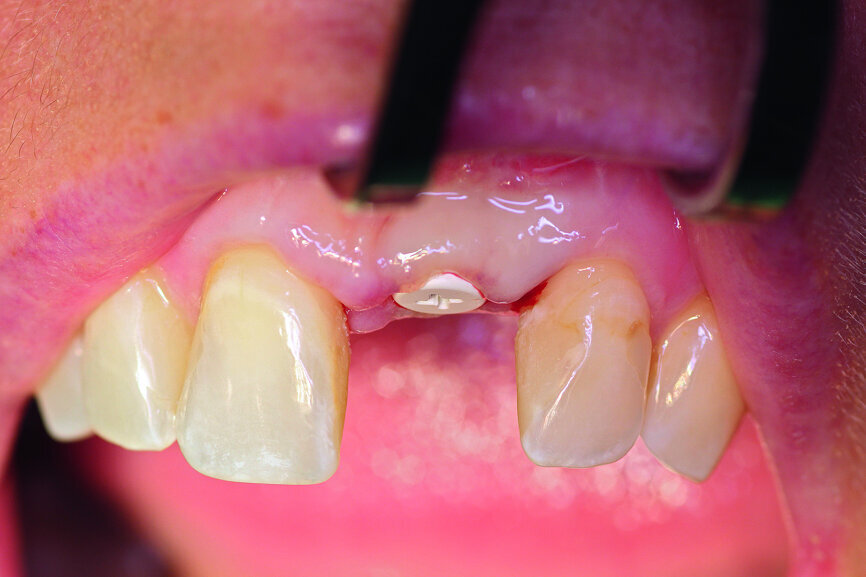

Fig. 4: The implant site was uncovered after five months.

Fig. 5a: A two-piece ceramic implant was inserted.

Fig. 5b: A two-piece ceramic implant was inserted.

After extraction of tooth #21, the apical granulation tissue was excochleated through a semilunar incision (Fig. 3). A two-stage procedure was performed to prevent failure of osseointegration of the ceramic implant and to preserve the soft-tissue structures (papillae and attached gingiva). A claspless prosthesis made from Valplast (Valplast International) served as a temporary restoration. The implant site in region #21 was uncovered after five months (Fig. 4). A two-piece ceramic implant (diameter: 4.2 mm; length: 12.0 mm) was then inserted (Figs. 5a & b). The guidelines for implant placement in the aesthetic zone and the drilling procedure specified by the manufacturer were observed.13, 14 Both vertical and transverse insertion depth are decisive for prosthetic success. The implant can be placed between 1.6 mm and 0.6 mm supracrestally because of a special thermal etching procedure in the collar region; the insertion depth is determined by the gingival height and the existing bone of the adjacent teeth. The implant positioning should be approximately 2–3 mm subgingivally because the abutments are added 1 mm above implant shoulder level. Transversal bone augmentation was performed with a mixture of autogenous bone chips (retrieved from the retromolar mandible), xenograft (Geistlich Bio-Oss, Geistlich Biomaterials) and guided bone regeneration (Jason membrane, botiss biomaterials; Figs. 6a & b). The exposure was performed after four months using a PEEK gingiva former (Fig. 7).